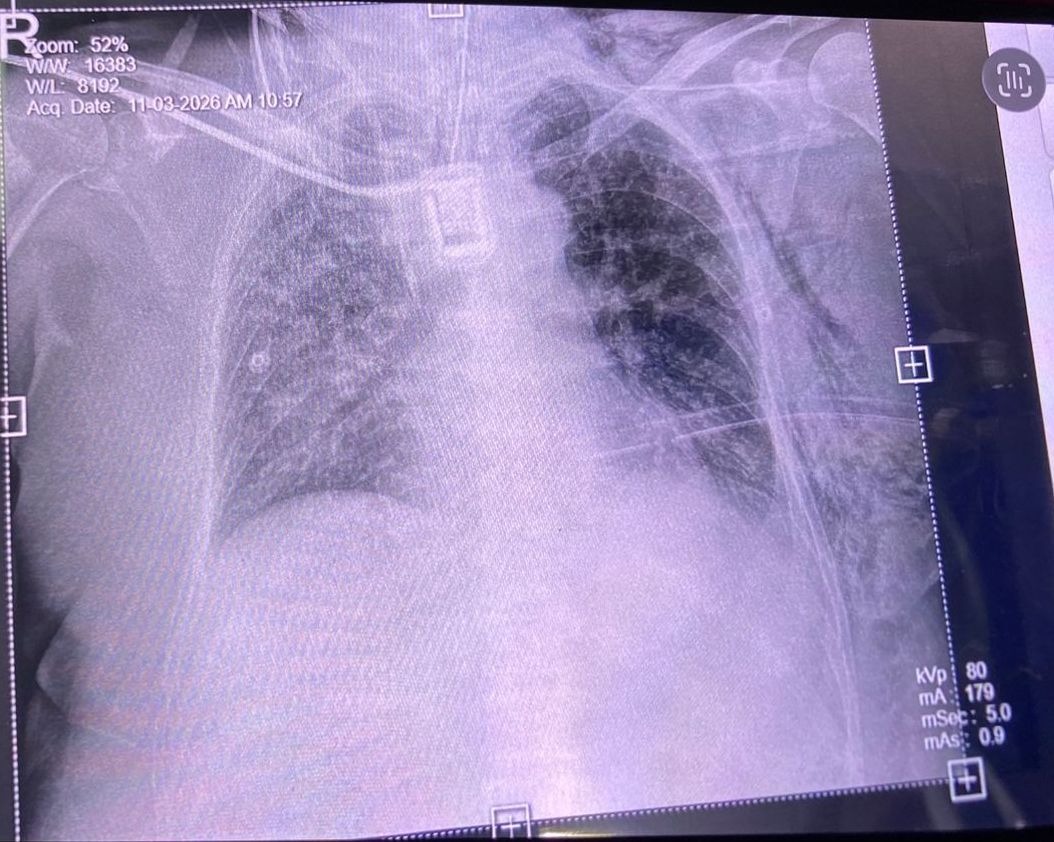

My father is a liver transplant patient. In 2023, he was diagnosed with liver cancer (Hepatocellular Carcinoma) and underwent chemotherapy twice. In 2024, with the help of a donor, he successfully underwent a liver transplant surgery. Unfortunately, after the surgery he developed complications, including bile leakage, and had to undergo ERCP stenting five times at three-month intervals.

During this difficult time, he was also diagnosed with lung metastasis and underwent proton therapy (a type of radiation treatment).

On March 5th this year, his condition suddenly worsened and he had to be taken to the hospital in an emergency. He is now diagnosed with sepsis and is in very critical condition. Dr. said, since he is a post-transplant patient, his immune system is very weak, and the treatment will take time. Although there are signs of improvement, his recovery is slow and he will need t stay in the ICU for a long period.